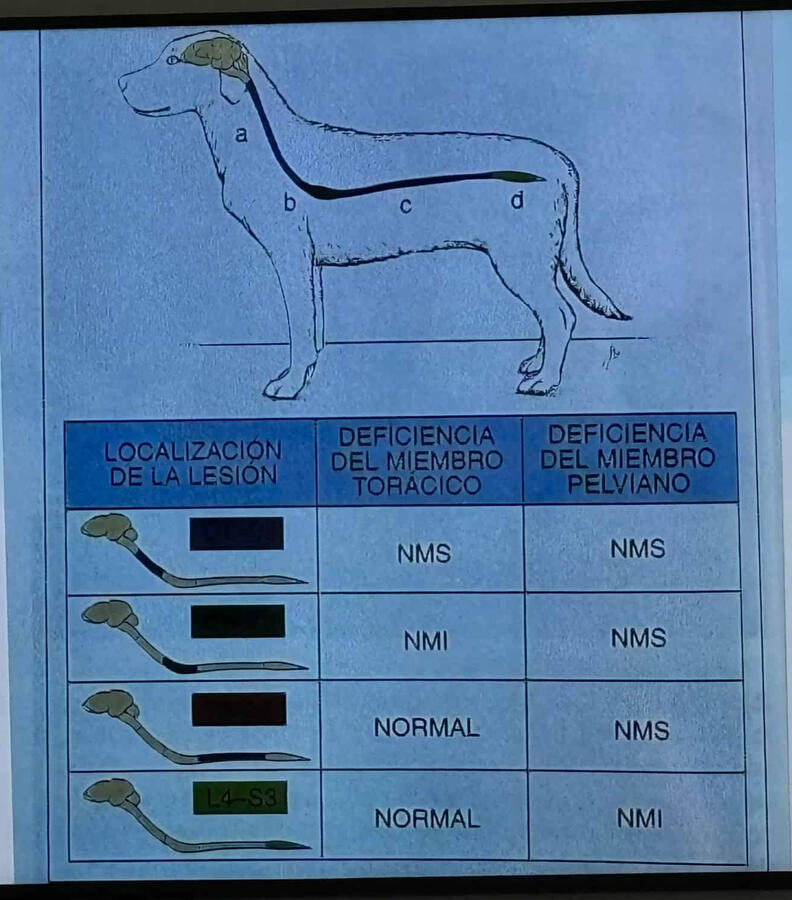

In addition, I continuously train in the areas of orthopedics, traumatology, and pain control. General and traumatological surgery.